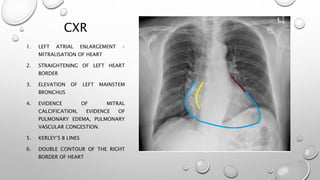

CXR

1. LEFT ATRIAL ENLARGEMENT –

MITRALISATION OF HEART

2. STRAIGHTENING OF LEFT HEART

BORDER

3. ELEVATION OF LEFT MAINSTEM

BRONCHUS

4. EVIDENCE OF MITRAL

CALCIFICATION, EVIDENCE OF

PULMONARY EDEMA, PULMONARY

VASCULAR CONGESTION.

5. KERLEY’S B LINES

6. DOUBLE CONTOUR OF THE RIGHT

BORDER OF HEART